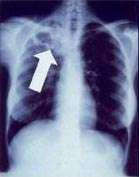

Radiology (X-rays) is used in the diagnosis of tuberculosis. Abnormalities on chest radiographs may be suggestive of, but are never diagnostic of, TB but can be used to rule out pulmonary TB.

In active pulmonary TB, infiltrates or consolidations and/or cavities are often seen in the upper lungs with or without mediastinal or hilar lymphadenopathy.[1] However, lesions may appear anywhere in the lungs. In HIV and other immunosuppressed persons, any abnormality may indicate TB or the chest X-ray may even appear entirely normal.[1]

Abnormalities on chest radiographs may be suggestive of, but are never diagnostic of, TB.[1] However, chest radiographs may be used to rule out the possibility of pulmonary TB in a person who has a positive reaction to the tuberculin skin test and no symptoms of disease.